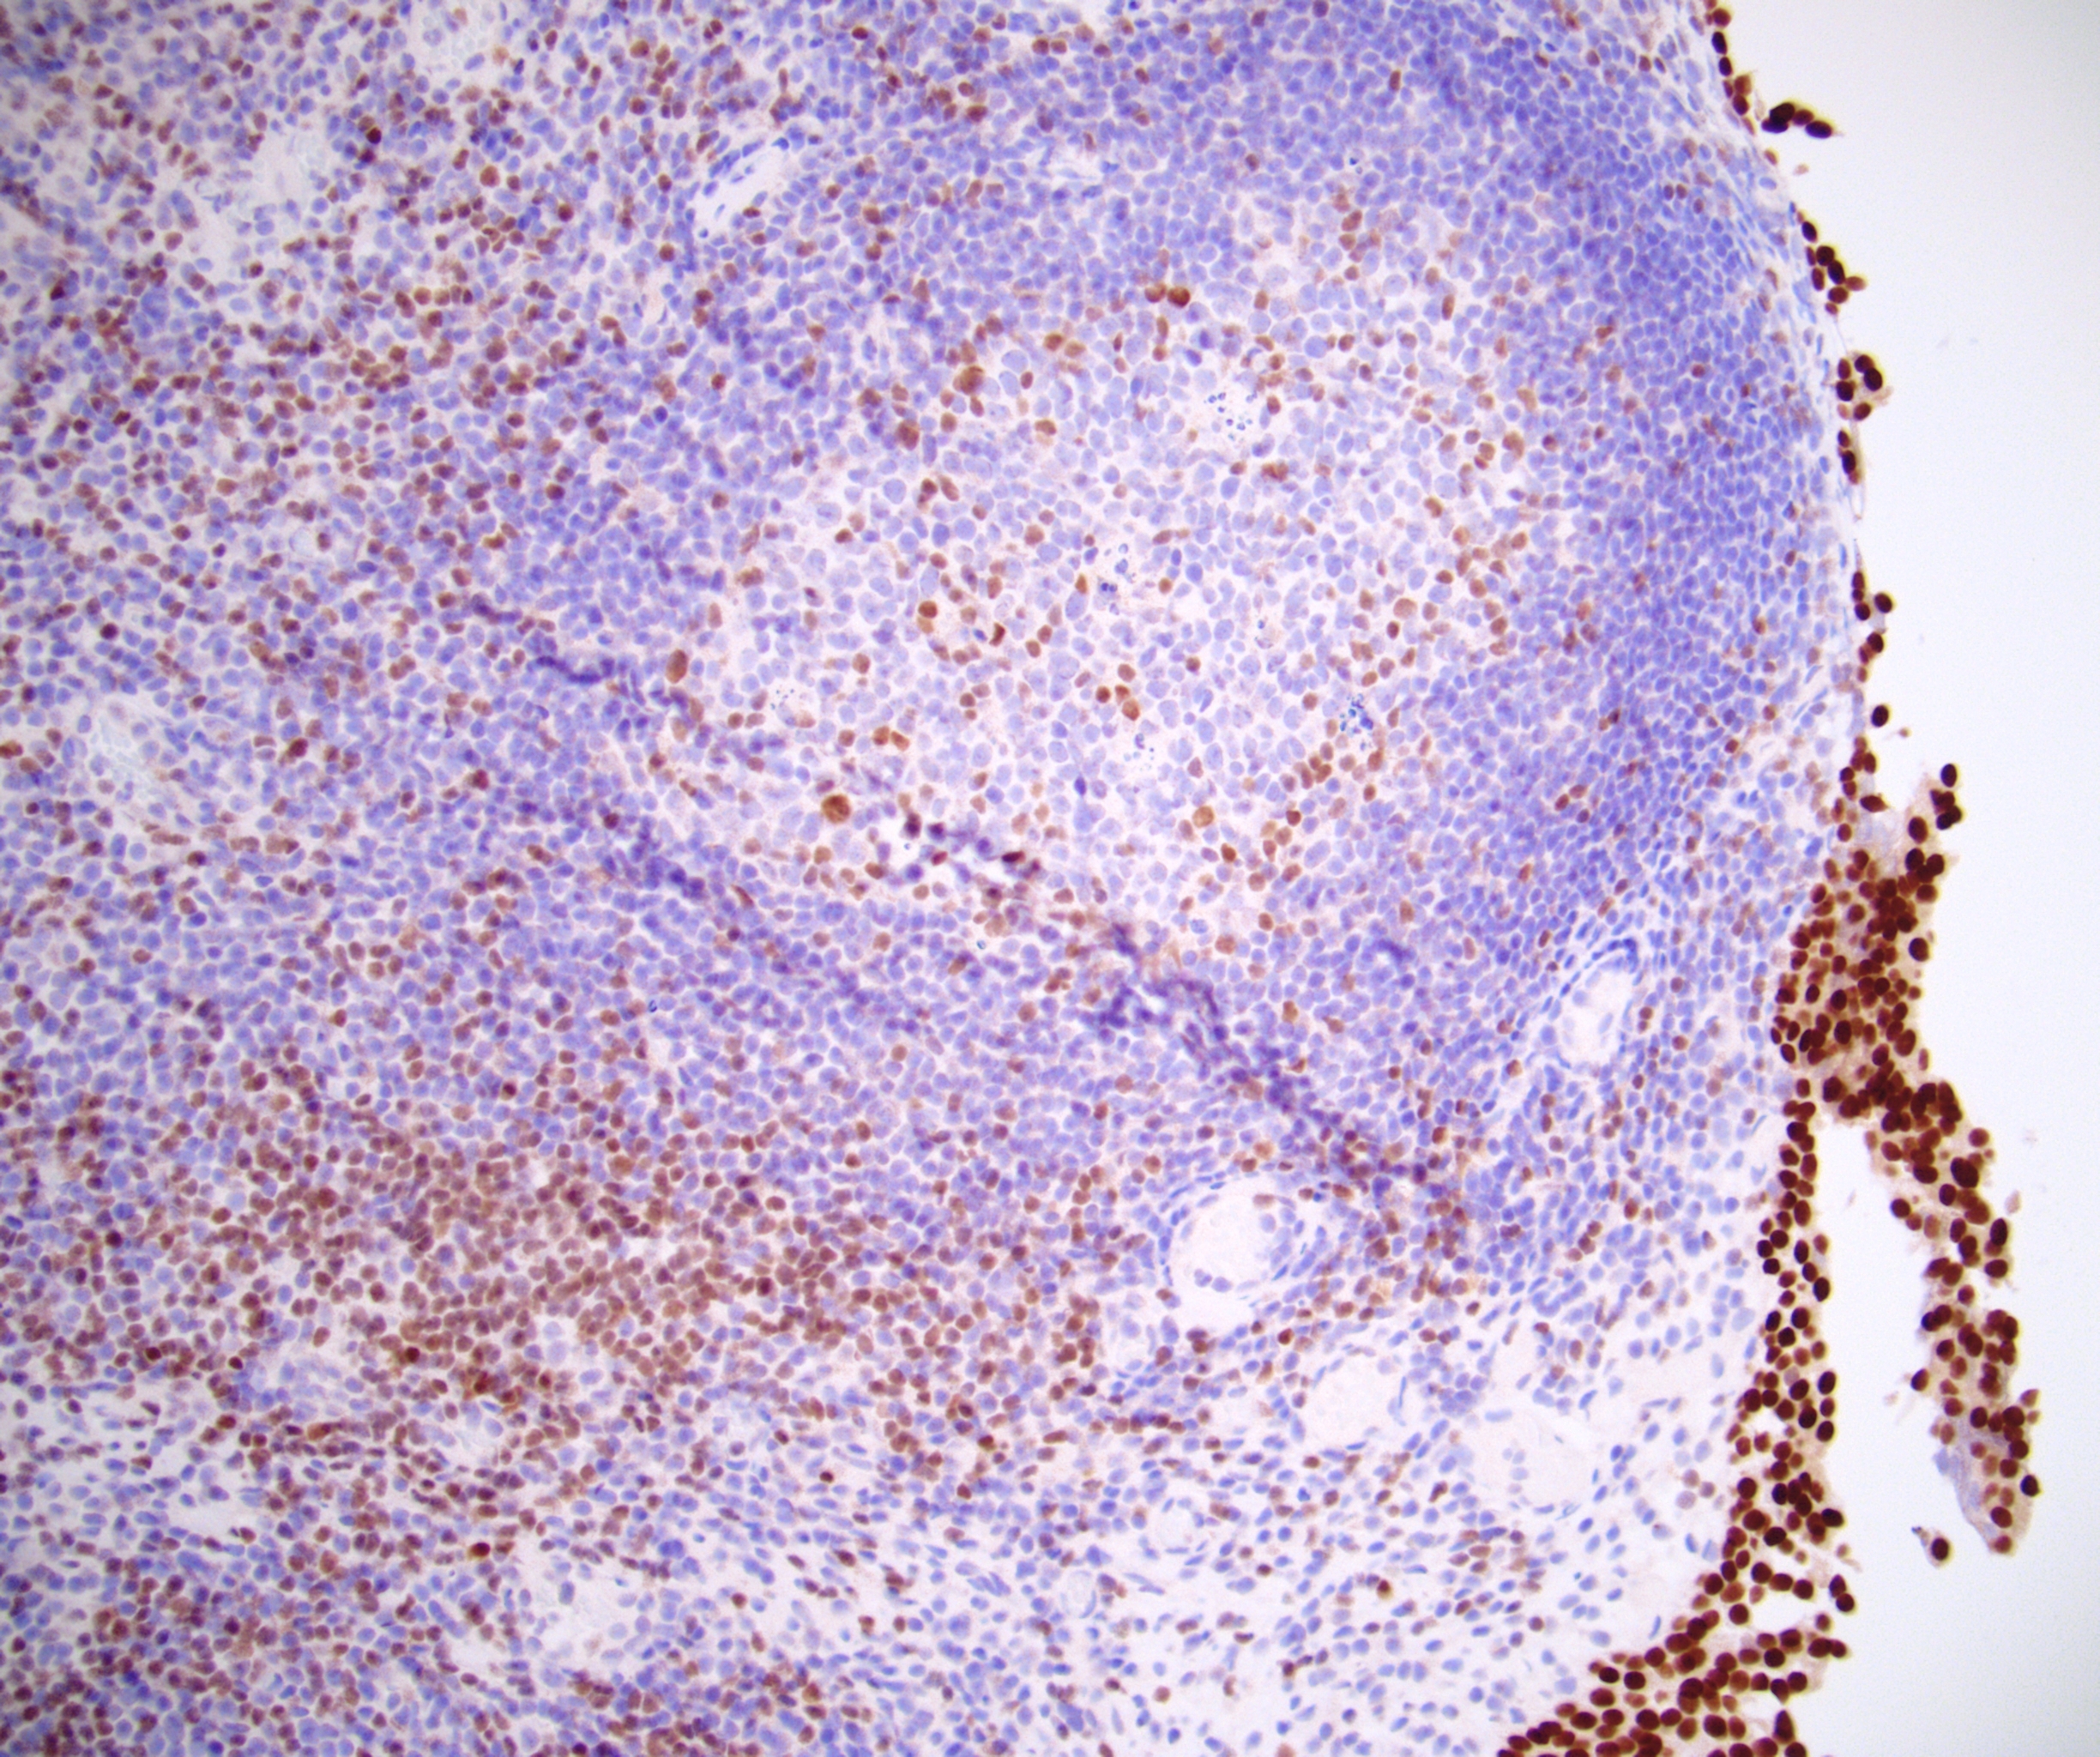

Microscopic (histologic) images

Contributed by Emily S. Reisenbichler, M.D., Andrey Bychkov, M.D., Ph.D., Maria Tretiakova, M.D., Ph.D. and Debra Zynger, M.D.

- Peripheral T cell lymphoma, NOS (30%) (Am J Clin Pathol 2010;133:281)